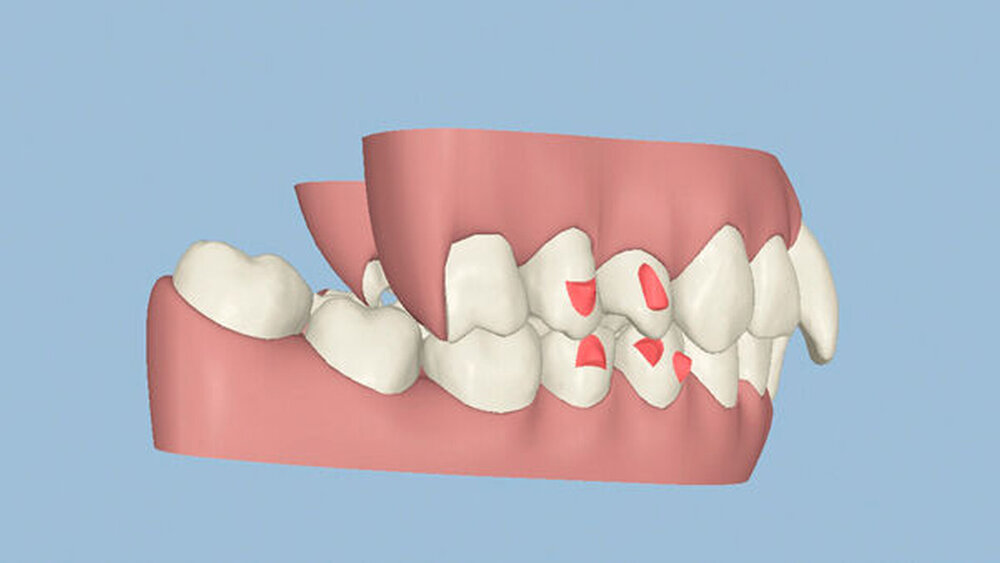

Um einen kompletten Lückenschluss im Oberkiefer zu ermöglichen, musste im Unterkieferfrontzahnbereich zusätzlich zur Derotation und Positionierung der Zähne – insbesondere Zahn 41 – von approximaler Schmelzreduktion, kurz ASR , Gebrauch gemacht werden, um einer Tonn`schen Diskrepanz entgegenzuwirken (siehe dazu Abbildung 7 auf Seite xy).